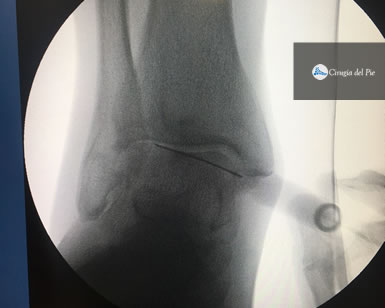

Se obtiene de la sangre del propio paciente. La muestra es procesada en forma específica en una centrífuga, separando las distintas fracciones de la sangre. Una de ellas, es el plasma con concentrado de plaquetas. La característica principal de esta fracción es que presenta una gran cantidad de factores de crecimiento que promueven la migración y diferenciación celular para la reparación de los tejidos. Este material puede procesarse para ser utilizado en forma líquida o gelatinosa, pudiendo ser aplicado en tratamientos de cura avanzada de heridas y úlceras, también a nivel muscular, tendinoso, ligamentario y fracturas, como así también en forma intraarticular. Habitualmente lo hacemos en forma ambulatoria.

Plasma rico en plaquetas Dr Masaragian